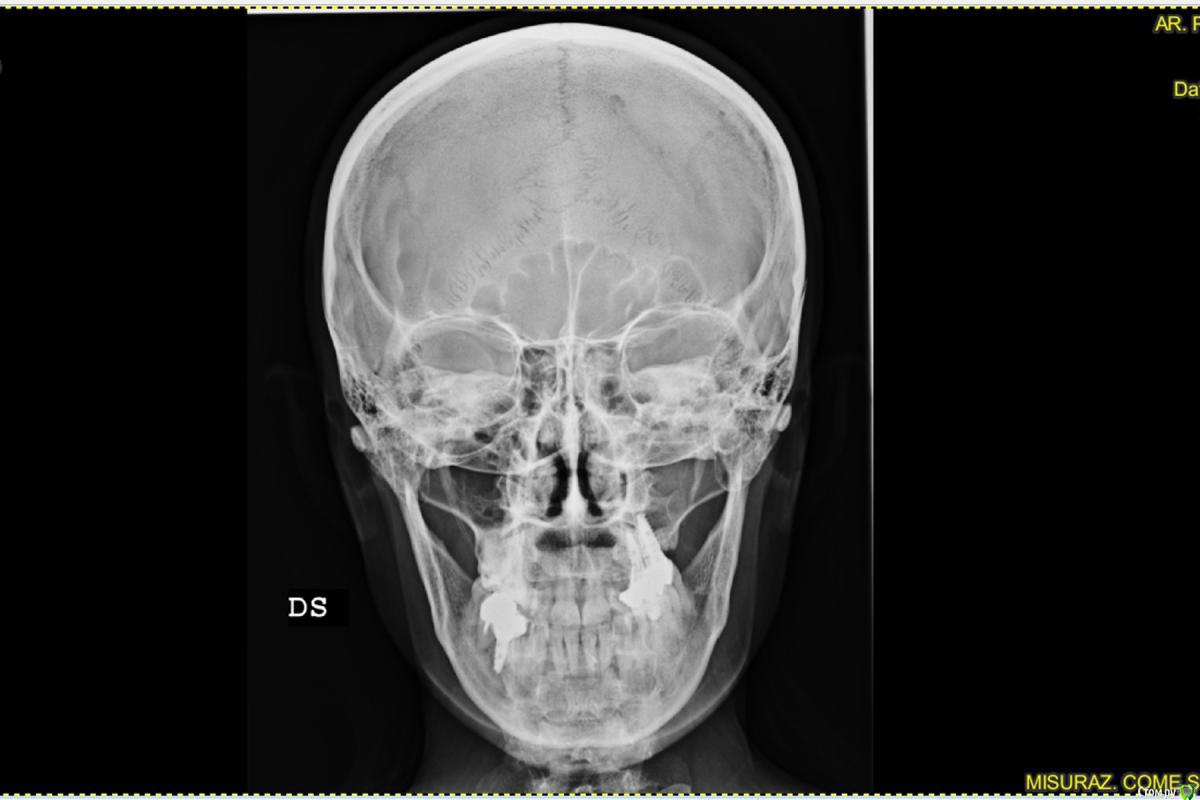

irada Опубликовано 17 декабря, 2019 Поделиться Опубликовано 17 декабря, 2019 Добрый вечер. У меня критическая ситуация. Месяц назад попопала в скорую с температурой и головной болью,выделения из носа не очень обильные но резккий запах, выяснилось -гайморит с левой стороны , сделала курс уколов антибиотиками, но через 2 недели опять поднялась температура и те же самые симптомы , лор отправил делать сникок зубов. У меня как раз с левой стороны подряд 3 импланта сверху , после клыка установлены 3 импланта где жевательные зубы, имланиы были установлены 3 года назад, одновременно с синус лифтингом, врачь говорит что корни имплантов воспалены, вернее кость, там хроническое воспаление, которое вызывает гаймлрит и нужно удалять импланты , чистить, наращивать кость, через время делать новые.Если ли какие то альтернативы? или нет шансов сохранить имплант? Ссылка на комментарий

АнтонТЛТ Опубликовано 17 декабря, 2019 Поделиться Опубликовано 17 декабря, 2019 Лучше сделать компьютерную томографию. Есть подозрение, что проблема исходит от зубов соседствующих с имплантатами. 2 Ссылка на комментарий

red_butler Опубликовано 18 декабря, 2019 Поделиться Опубликовано 18 декабря, 2019 + 1 Кт с придаточными пазухами носа сделайте Ссылка на комментарий

irada Опубликовано 21 декабря, 2019 Автор Поделиться Опубликовано 21 декабря, 2019 что-то по этому снимку и кости то вокруг имплантатов не видно, очень плохое качество.Сделайте дентальную компьютерную томографию верхней челюсти, чтобы туда вошли пазухи с соустьями.Но что-то мне подсказывает, что там все на удаление.мне точно пока не могут сказать нужно ли удалять, сказали может придется как то восстанавливать мембрату потому что имлант пробил синус. и что у меня кость гниет. что надо отрезать кусочек корня импланта восттанавливать мембрану. наращивать кость. но при этом не удалять имплант. я просто первый раз о такой операции слышу Ссылка на комментарий

колесников Опубликовано 22 декабря, 2019 Поделиться Опубликовано 22 декабря, 2019 Очень тонкая кость может быть не видна снимке,в том что имплант на снимке выступает в полость пазухи ,ничего криминального нет,итальянские коллеги только так и ставят . То что вам предложили,довольно травматичная операция,необходимо оценить ее целесообразность, Ссылка на комментарий